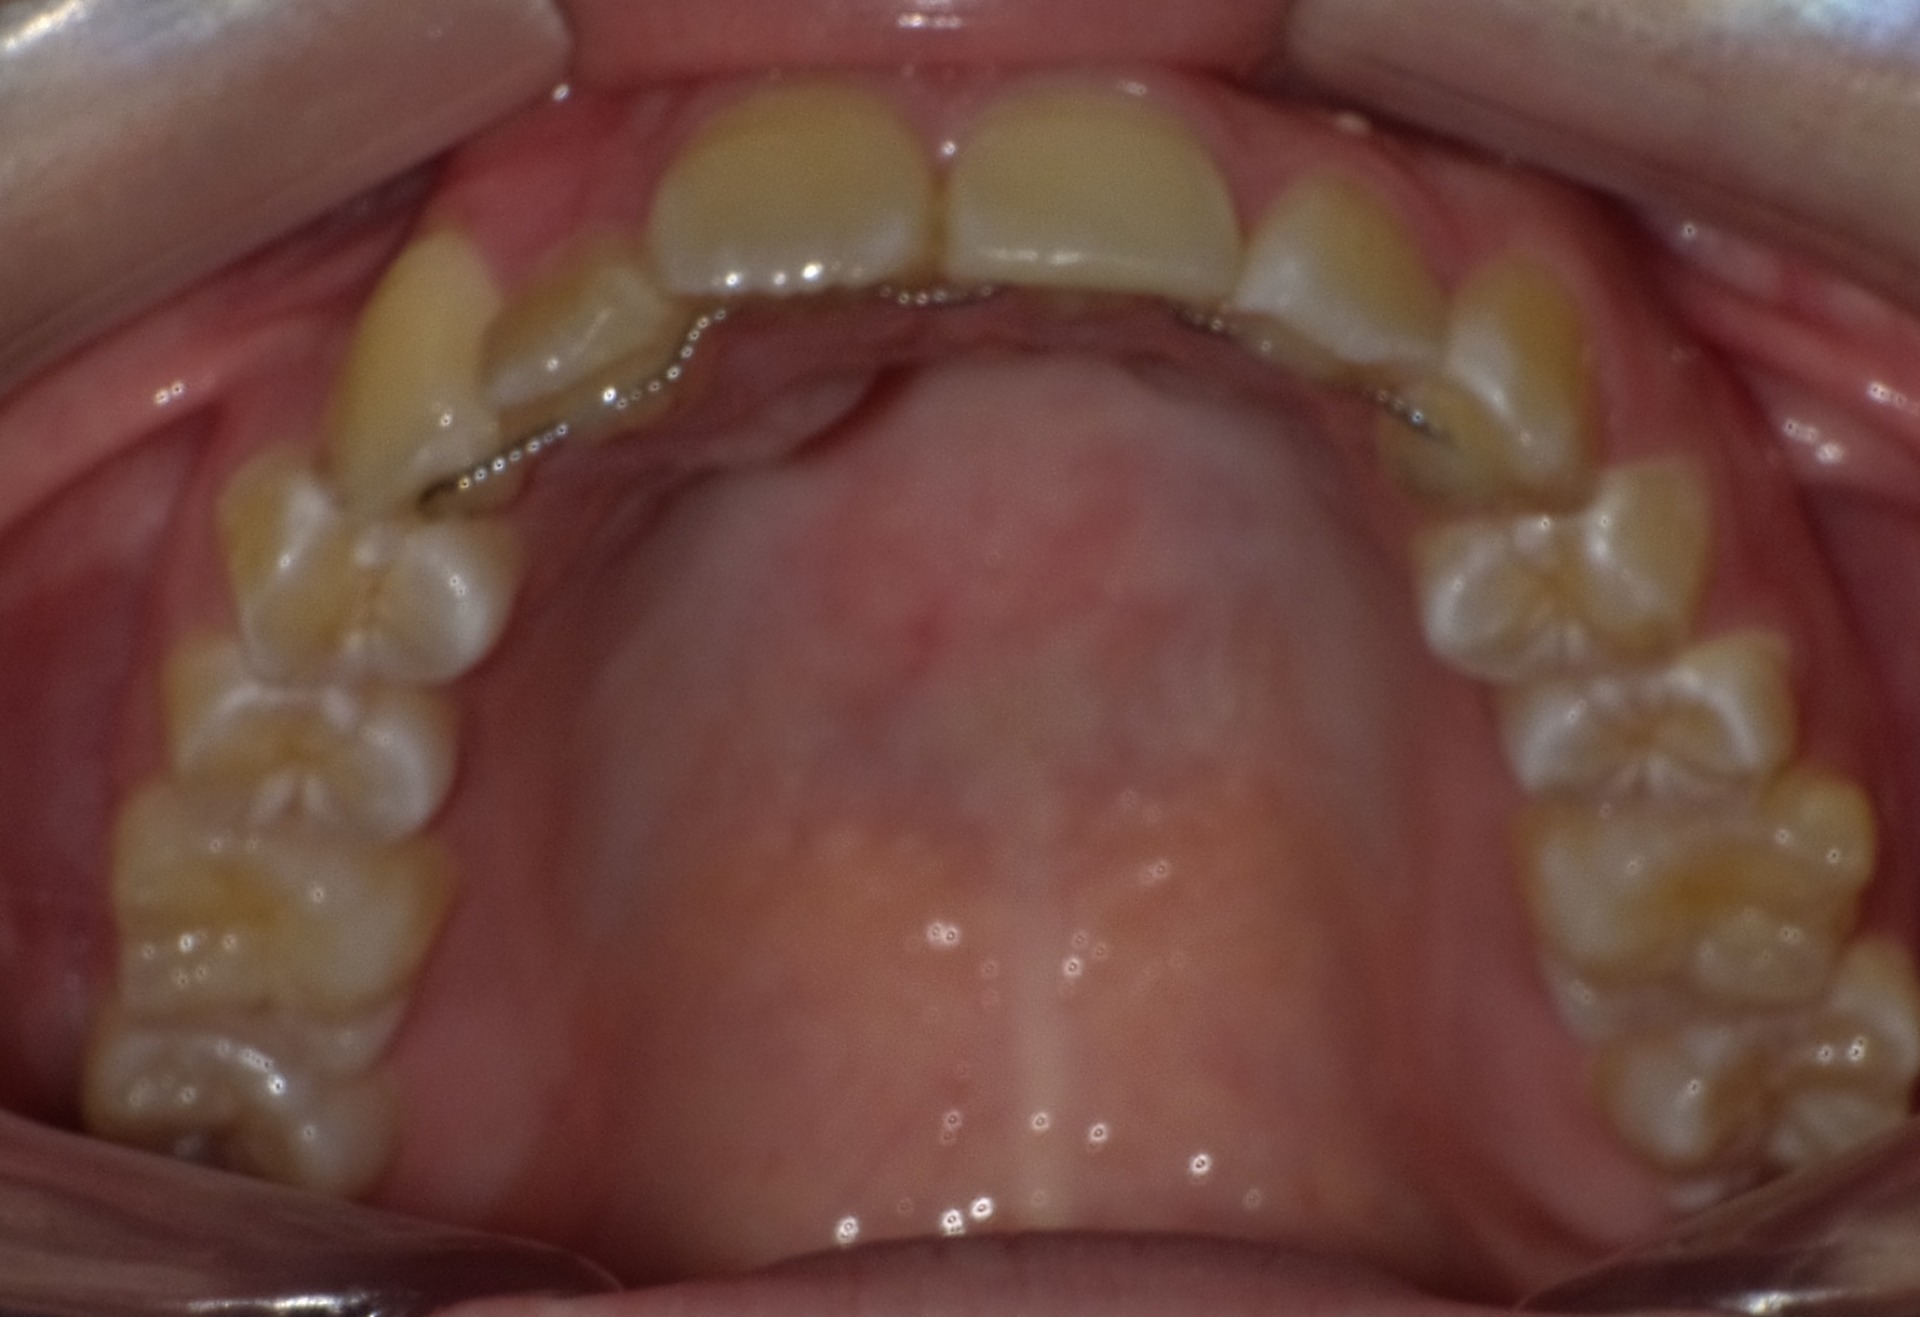

矯正前

| 症状 | 左上2番3番逆転症例 |

|---|---|

| 通院時の 年齢 |

10才2ヶ月〜21才2ヶ月 |

| 通院回数 | 142回 |

| 通院目的 | 永久歯を抜かずに歯並びを治したい。 |

| 処置内容 | プレート拡大処置・マルチブラケット装置・クリアアライナー・ディスタライザー |

| 費用 | 基本料金 税抜625,000円 (通院時2,100円〜4,400円の調整料を頂いていました。) ※過去の治療の料金ですので、現在とは異なります。 |

| デメリット・院長コメント | 永久歯を抜かない治療のデメリットは、治療期間が長いことです。 ただし、その後の人生の長さを考えると、健全な小臼歯を2本または4本抜歯の矯正治療よりも、はるかにメリットがあるといえます。 また、アーチが小さくならないので、舌が後ろに押し込まれないためいびき防止につながり睡眠の質の向上にもつながります。 |